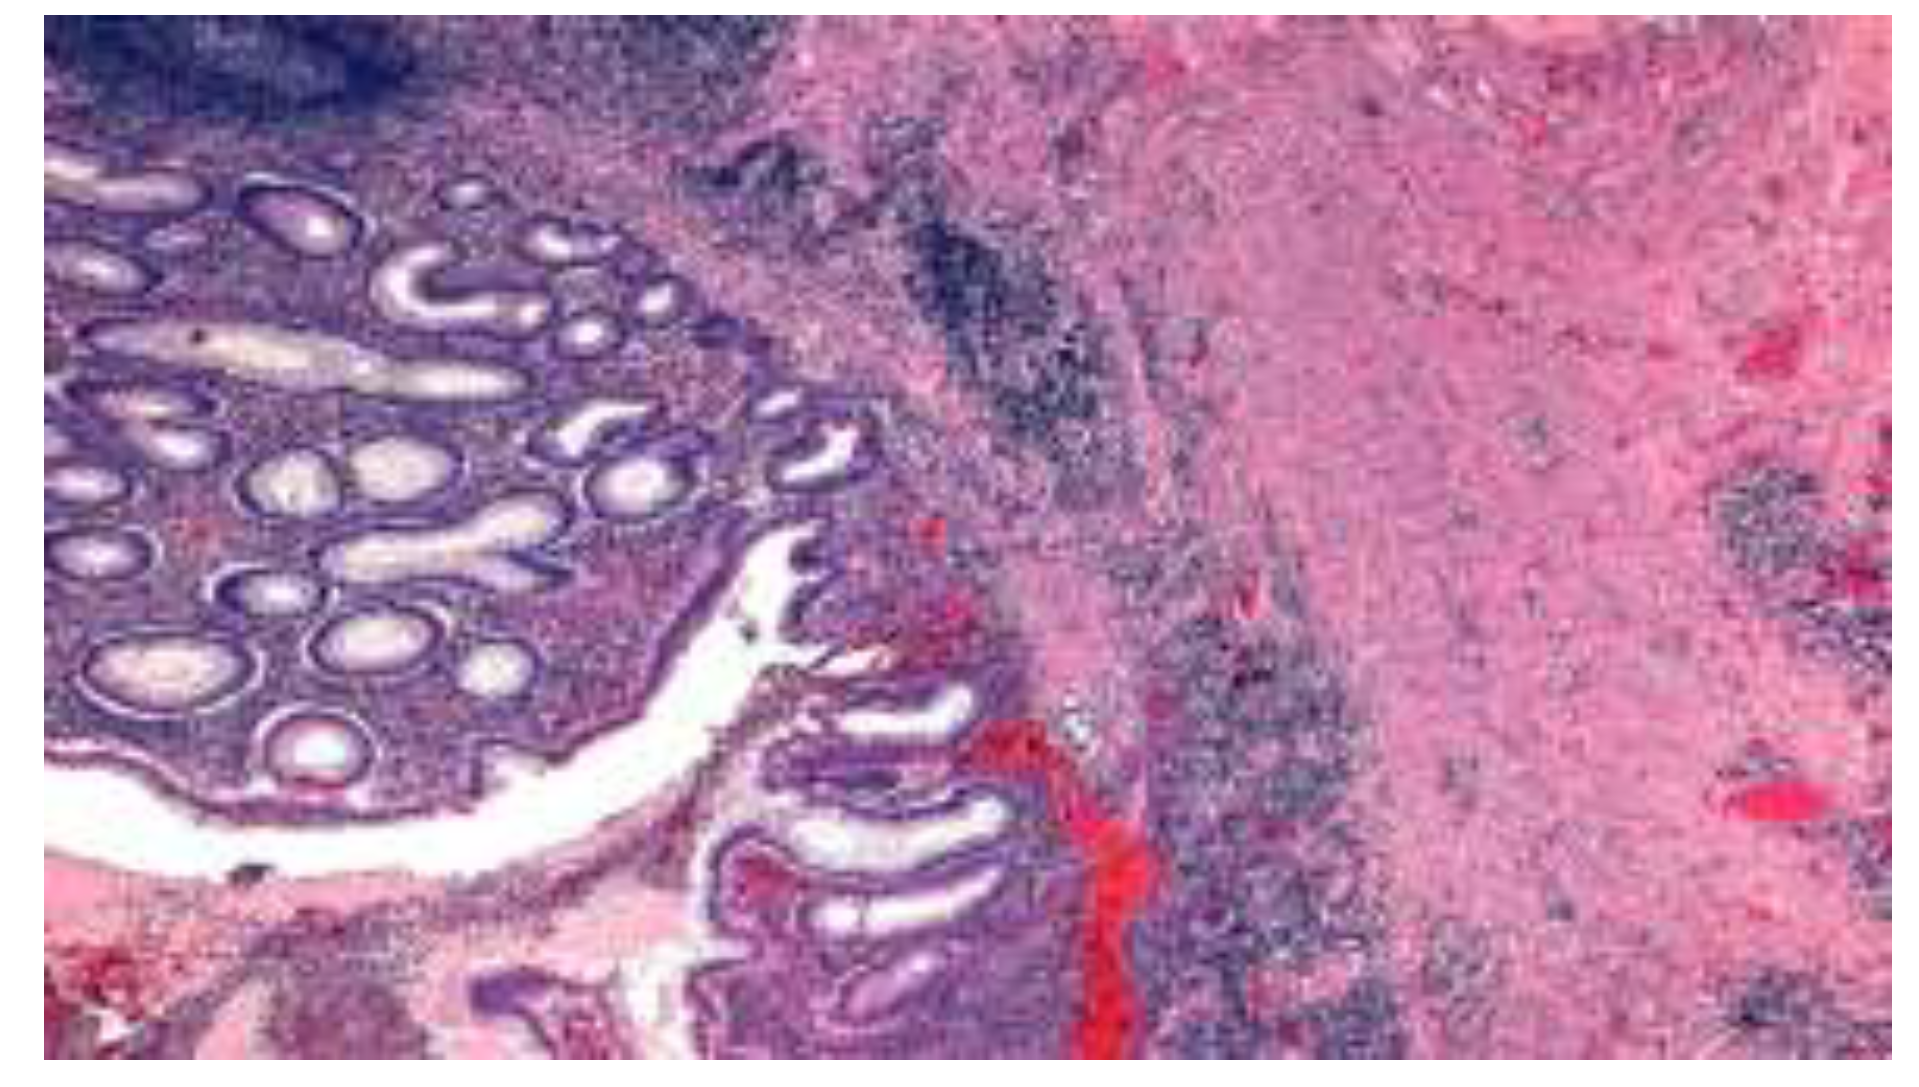

- the focal or the discontinuous inflammation of the mucosa with or without the lengthening and distortion of the crypts, with predomination of histiocytes and lymphocytes in the inflammatory infiltrate.

- epithelioid granulomas.

- the presence of lymphoid aggregates at the border of the muscularis propria and subserosa, associated with the infiltration of the muscular layer by mononuclear leukocytes in most cases [30].